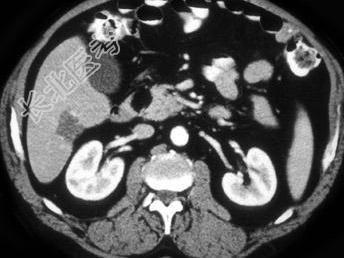

- 单项选择题结合图像,该胰腺团块, 最不可能的诊断为 ( )

A、肉瘤

B、脂肪瘤

C、胰腺囊肿

D、以上都有可能

E、以上都不是